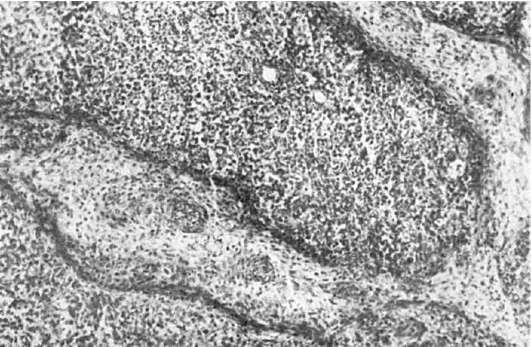

При гранулематозном периодонтите по периферии околоверхушечного скопления грануляционной ткани образуется фиброзная капсула, которая плотно спаяна с тканями, окружающими верхушку зуба. Этот вариант гранулематозного периодонтита носит название простой гранулемы. Среди клеточного пролиферата преобладают фибробласты, макрофаги, встречаются лимфоциты, плазматические, ксантомные клетки, кристаллы холестерина, иногда гигантские клетки типа клеток инородных тел. Костная ткань альвеолярного отростка, соответствующая расположению гранулемы, подвергается резорбции. При обострении воспаления гранулема может нагнаиваться. Наиболее часто встречается второй вариант гранулематозного периодонтита -сложная, или эпителиальная, гранулема (рис. 353). Ее отличие от простой гранулемы заключается в том, что в ней

образуются тяжи многослойного плоского эпителия, пронизывающего грануляционную ткань. Происхождение эпителия в гранулеме связывают с пролиферацией остатков одонтогенного эпителия (островки Малассе). Третий вариант гранулематозного периодонтита - кистогранулема. Морфогенетически она связана с эпителиальной гранулемой и представляет собой полость с эпителиальной выстилкой. Формирование кистогранулемы связывают с нагноением, дистрофическими и некробиотическими процессами в грануляционной ткани. Кистогранулема может

Рис.

353. Хронический периодонтит. Эпителиальная гранулема